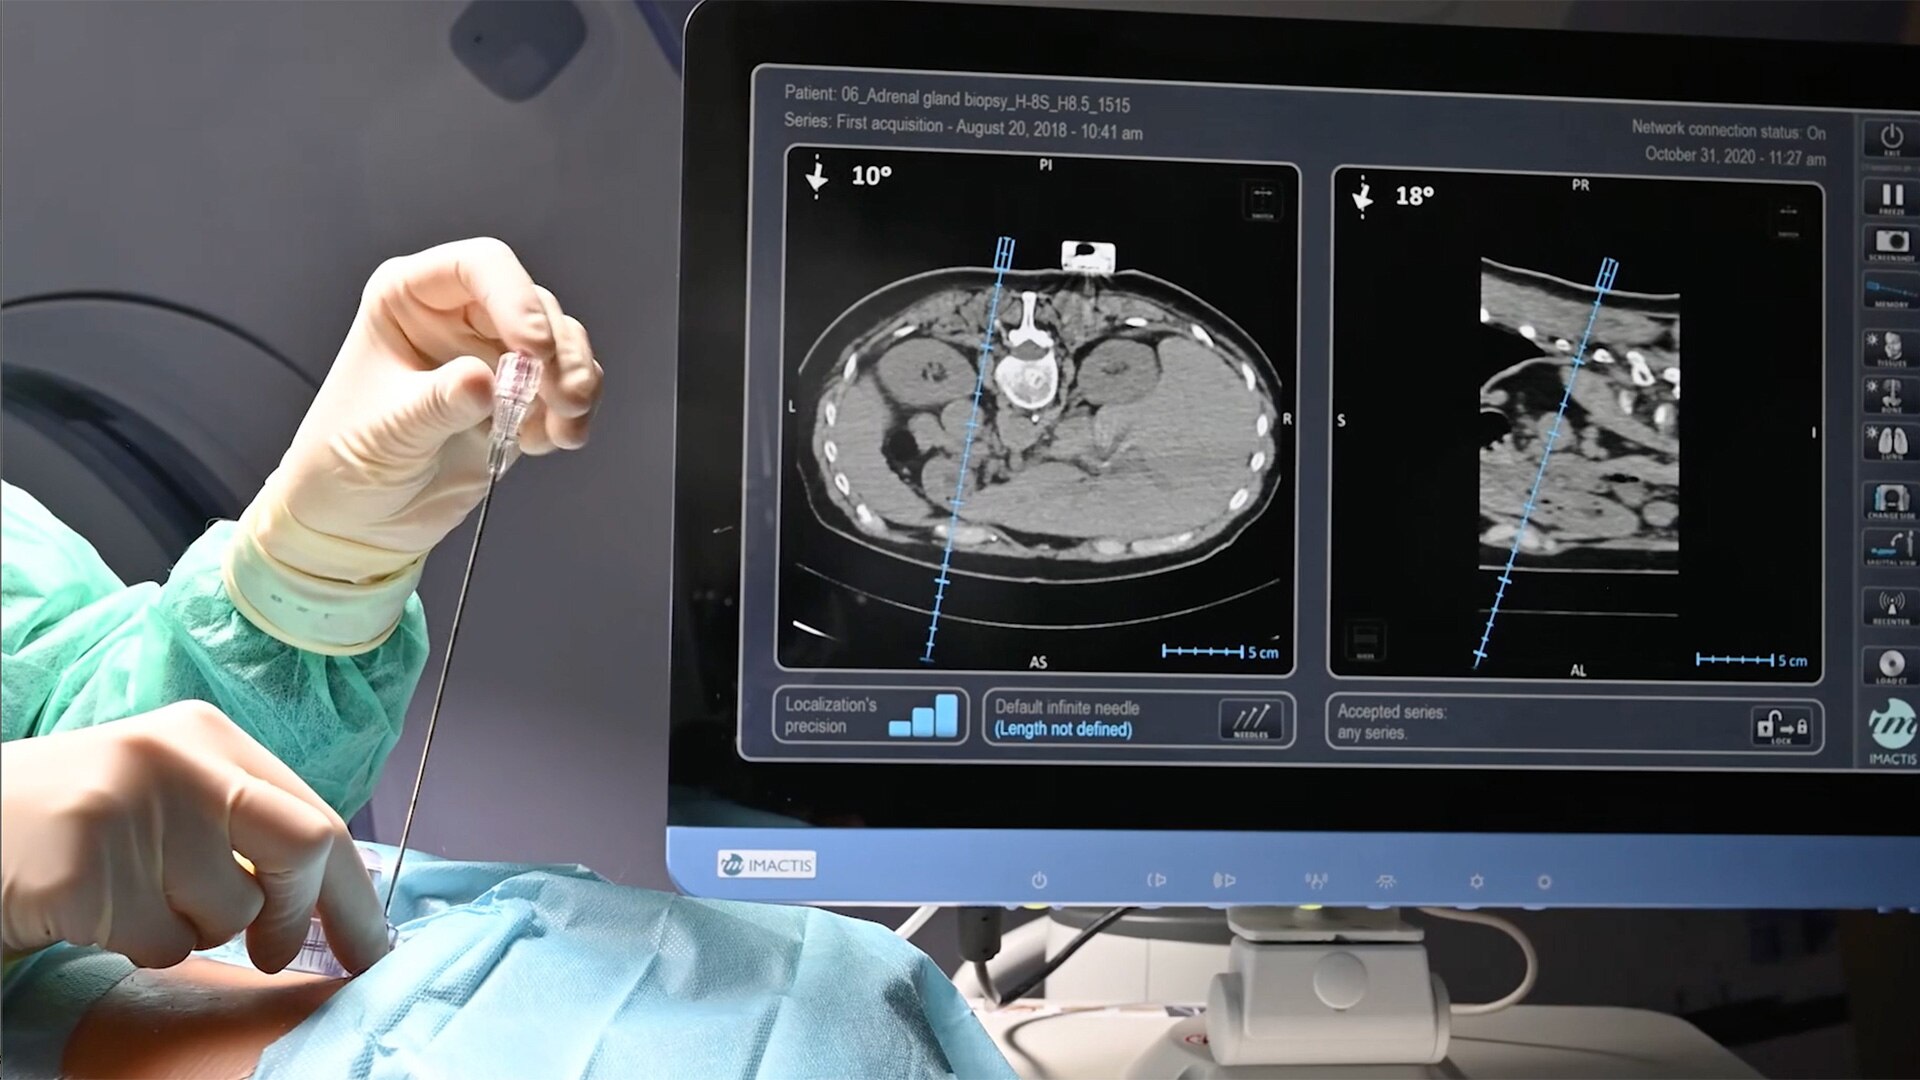

Imactis® CT-Navigation™

Planning and navigation solution for interventional percutaneous radiology.

Improve accuracy to reach target and avoid critical structures and organs¹

Ideal to use with various percutaneous interventions² with various complexity

Quick set-up of less than 5 min³, and a short learning curve of 6.6⁴ cases on average

Imactis® CT-Navigation™ is an electromagnetic (EM) navigation solution for CT-guided percutaneous procedures

Imactis® CT-Navigation™ is designed to radically improve efficiency of Interventional procedures for clinicians and hospitals by increasing their accuracy.